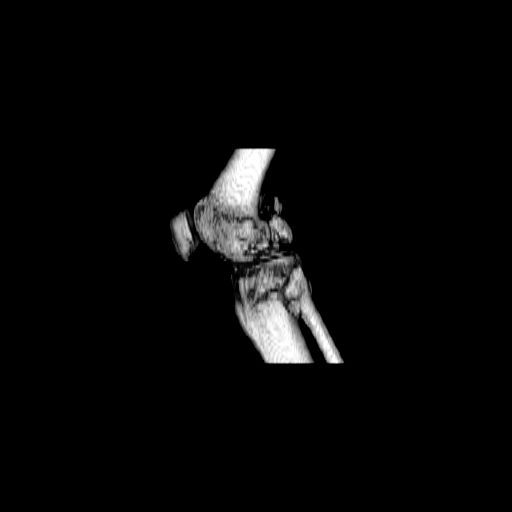

При внутрисуcтавных переломах трехмерные (3D) изображения, кроме красивого снимка, не дают полную информацию о состоянии отломков, самыми информативными являются корональные срезы на КТ и обычная длинная ренгенограмма конечности для сравнения оси конечности.

Фронтальные внутрисуставные переломы мыщельков бедра, так называемые Hoffa fracture, не частые, но встречающиеся переломы, в основном они связаны с травмой высокой энергией.

В зависимости от смещения рекомендуется сопоставление костных фрагментов с последующей жесткой фиксацией.